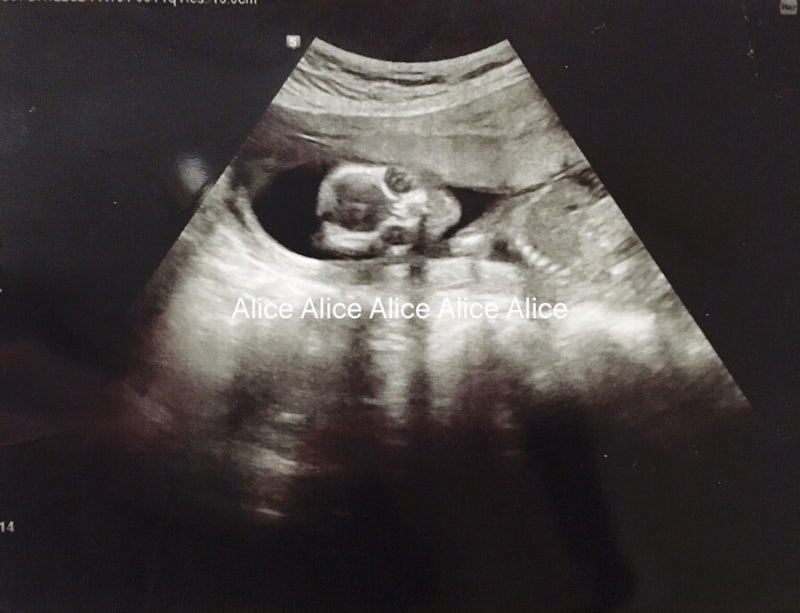

19주1일차 크기! 를 공유하면 정말 사진은 똥처럼 찍었지만 ㅋㅋ

이번 진료 때 탄탄이 하품하는 모습 찍혀서 올려보고…그럼 다음 진료 후기로 돌아갈게요!